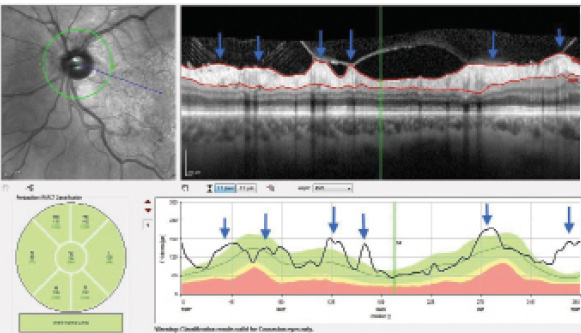

Figure 3. Vitreous traction on the RNFL can distort thickness measurements (blue arrows).